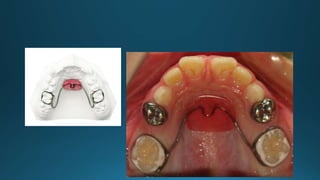

Lingual arch space maintainer

Platal arch appliance(Nance holding arch)